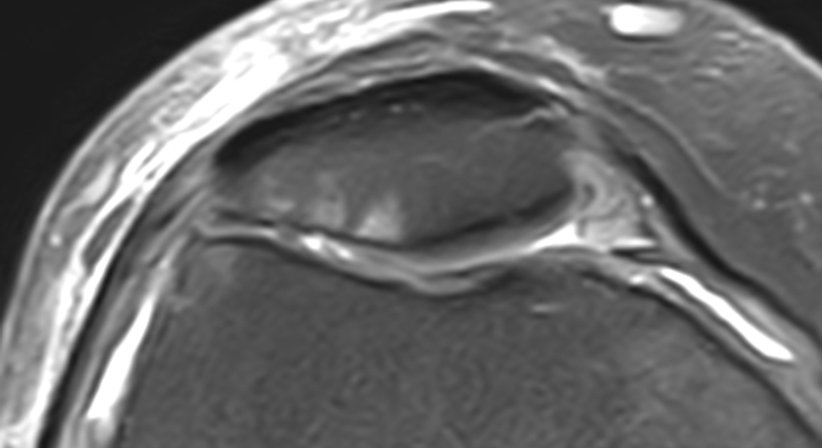

Knorpelschäden können von reiner Knorpelerweichung, Aufrauhung, Rillenbildung und Kraterbildung (=Knorpelulcus) bis hin zu totalem Knorpelverlust mit freiliegendem Knochen (=Knochenglatze) reichen.

In der Therapie kommen, je nach vorliegendem Stadium der Schäden, unterschiedliche Methoden zu Anwendung. Die angewandten Techniken reichen von intraartikulären Injektionskuren (ACP/PRP, Hyaluronsäure) und reiner Knorpelglättung über Mikrofrakturierung (=micro fracturing) und Mosaikplastik (=OATS) bis hin zu Knorpelzelltransplantationen (=MACT) und partiellem bzw. totalem künstlichen Gelenksersatz.